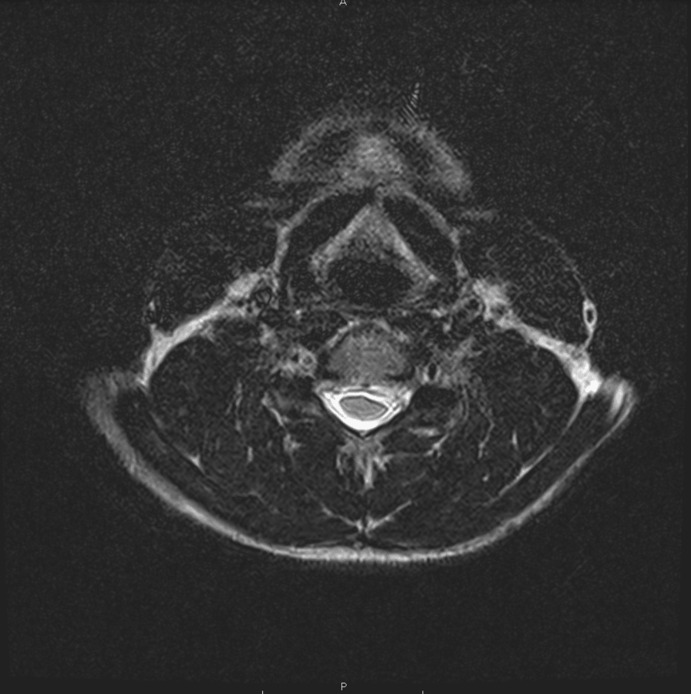

Case description: A 37-year-old male and Brazilian Jiu Jitsu athlete with cervical radiculopathy underwent a C5-C6 and C6-C7 discectomy with CTDR. The subject attended PT for 14 sessions across 16 weeks. Interventions included manual therapy (soft tissue and joint mobilization), therapeutic exercise targeting cervical spine, thoracic spine and upper extremity mobility and strength, and weightlifting body mechanics education. Radiographic confirmation of prosthesis placement and healing was monitored at postoperative weeks six and 12. The PT program was designed and progressed according to tissue healing timelines, subject response, clinical reasoning, and sport-specific demands.